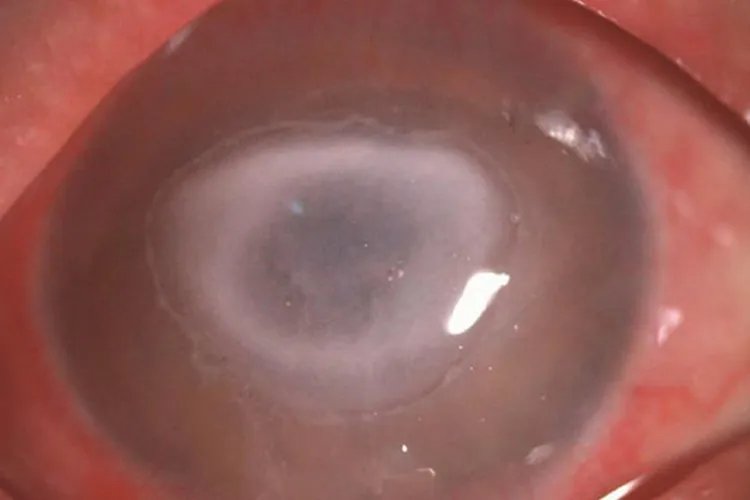

的有关信息介绍如下:概述角膜炎初期症状多见于角膜上皮病变,常为角膜溃疡、水疱、浑浊等。临床上可将角膜炎分为感染性角膜炎和非感染性角膜炎。角膜炎病因较多,与外界或内源性致病因素侵袭角膜组织相关。症状感染性结膜炎细菌性角膜炎本病起病急骤,病变早期表现为角膜上皮溃疡,溃疡下有边界模糊、致密的浸润灶,周围组织水肿。

非感染性角膜炎角膜基质炎发病初期为单侧,早期可见典型的扇形或弥漫性角膜炎症浸润,可伴有或不伴有角膜后沉着物。

浅层点状角膜炎初期症状不明显,一般见角膜上皮层出现结节状或灰色点状混沌。病因角膜炎分类不同,病因不一,感染性角膜炎由细菌感染引起,主要病原微生物为细菌、病毒、真菌和寄生虫。一些自身免疫性疾病,如类风湿关节炎可出现角膜病变。另外邻近组织的炎症可波及角膜,引发角膜炎症等。诊断根据典型的临床表现(如眼部刺激症状)及睫状充血、角膜浸润和角膜溃疡的形态特征等,角膜炎的临床诊断通常不困难,但应详细询问病史做病因诊断。治疗初期角膜炎的治疗原则是控制感染,减轻炎症反应,促进溃疡愈合和减轻瘢痕形成。细菌性角膜炎宜选用敏感的抗菌药物进行治疗。抗真菌药物仍是治疗真菌性角膜炎的重要手段,目前临床上多采用联合用药的方法以提高疗效,病情严重者可配合全身用药。单纯疱疹病毒性角膜炎可使用抗疱疹病毒药物治疗。